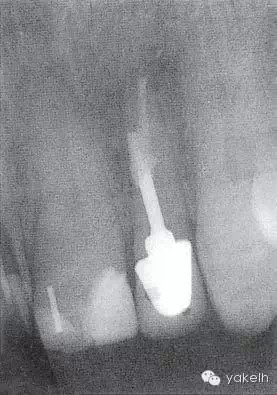

¤¤口外檢查可見(jiàn)顳下頜關(guān)節(jié)處輕微捻發(fā)音,開(kāi)口度、開(kāi)口型正常,無(wú)疼痛,未見(jiàn)其他異常??趦?nèi)檢查可見(jiàn)牙列中有部分良好的修復(fù)體,無(wú)齲壞;局部牙齦炎,探診出血,牙周探診深度不超過(guò)2mm。22唇側(cè)牙槽黏膜可見(jiàn)竇道(圖5.4.1a),輕微叩痛,竇道區(qū)捫痛,根尖X線片顯示牙根中部透射影,疑為樁穿孔(圖5.4.1b)。左上頜中切牙(21)和左上頜尖牙(23)對(duì)EPT和冷測(cè)試反應(yīng)正常。

圖 5.4.1(b)22根尖X線片,顯示樁穿孔側(cè)方的根周透射影。